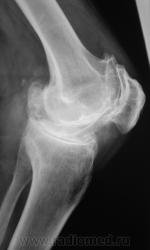

Боли в коленном суставе.

Деформирующий гонартроз 4 ст. или есть какой-то подвох? Двойной контур суставной поверхности медиального мыщелка бедра не Кениг ли случайно?

я бы по коссинской 2-3 ст. деформирующего артроза написала, ито 3 ст это когда уже совсем не прослеживается суставной щели, а здесь она есть.

Согласен с DR.RAD двухсоронний гонартроз 2-3степени.

Мне показалось, что суставная щель вовсе и не так уж сужена.А вот в пателло-феморальный суставе резкое сужение суставной щели.Выраженный субхондральный склероз, краевые остеофиты суставных поверхностей костей.А что там у Косинской по этому поводу написано, помните?